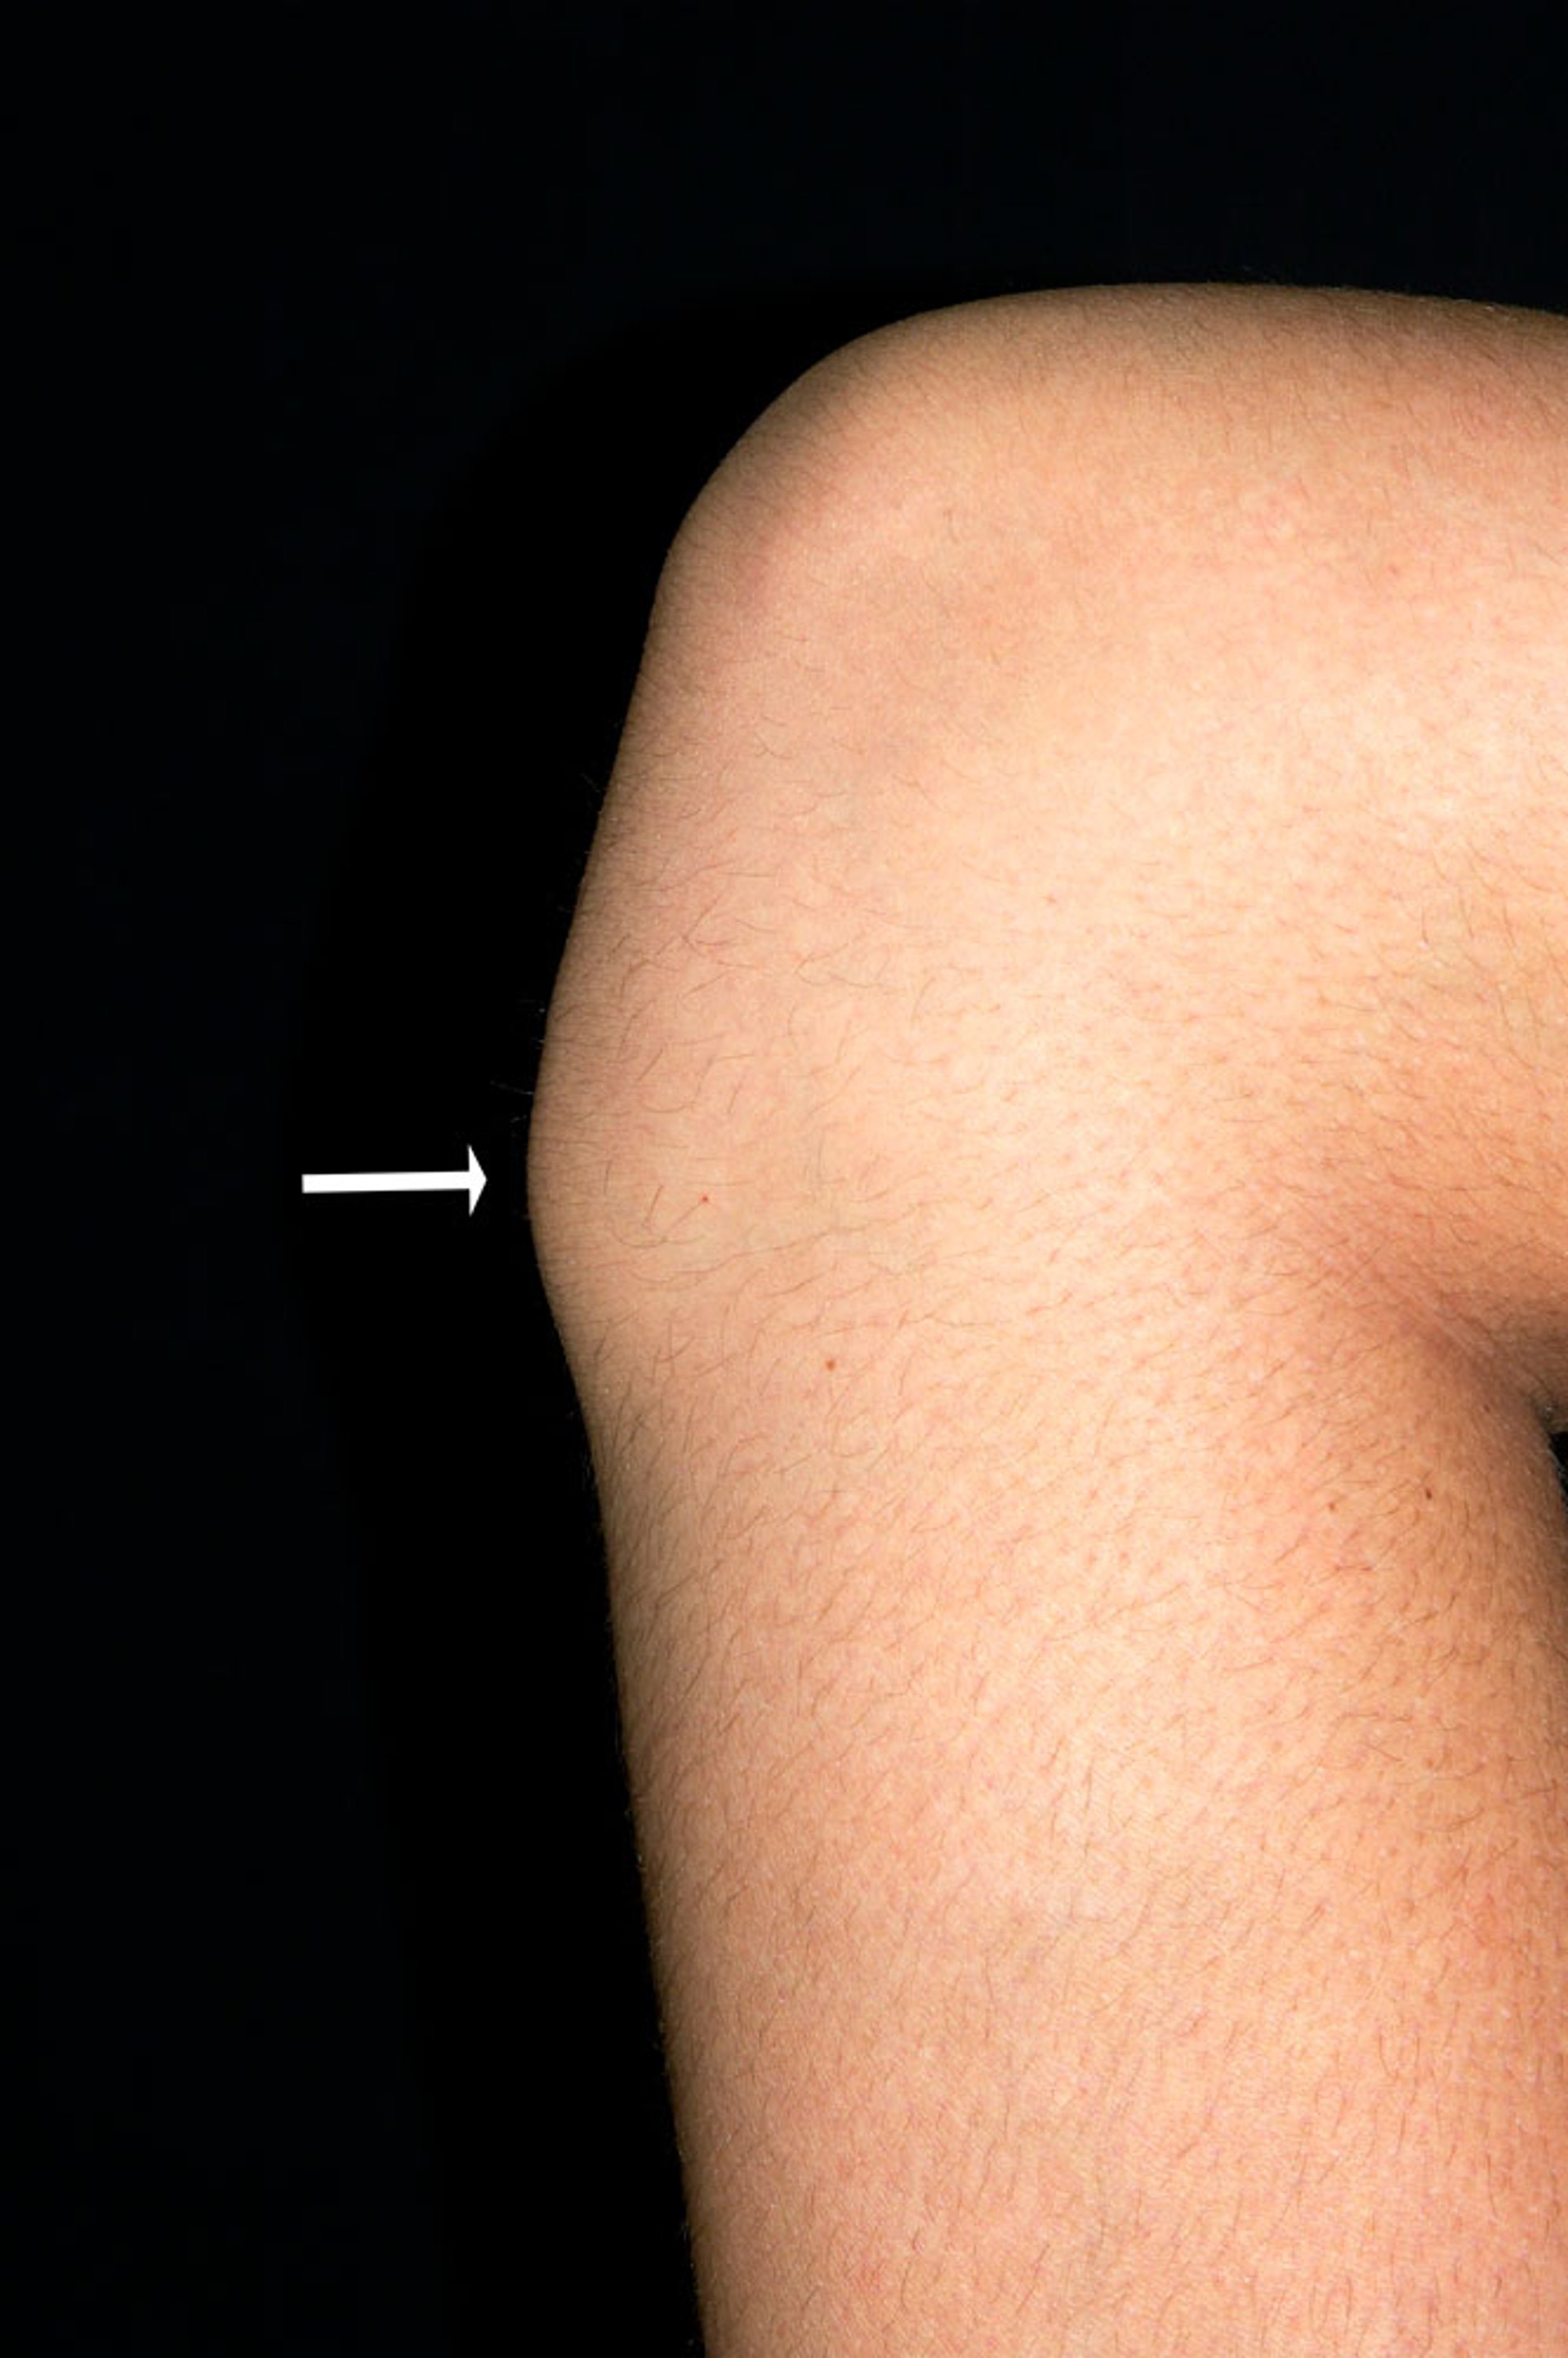

奥斯古德-施拉特病中的胫骨结节

这张照片显示了一名青少年男性的膝盖,由于奥斯古德-施洛特病而出现骨突出(胫骨结节,箭头所示)。